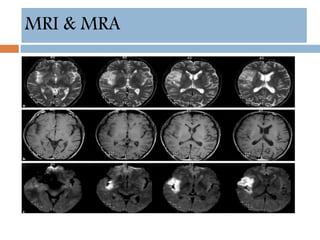

MRI & MRA